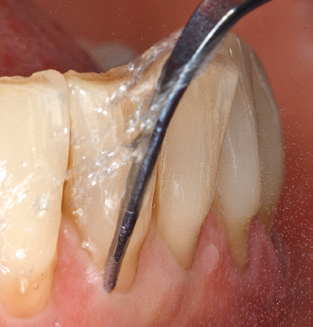

Dopo la pulizia meccanica delle superfici dei denti e degli impianti, le superfici dei denti naturali vengono pulite manualmente utilizzando strumenti manuali standard. Quando si esegue la pulizia manuale, è necessario prestare particolare attenzione a mantenere il corretto angolo di applicazione, un'adeguata nitidezza, un buon supporto e lavorare con la curette dall'apicale al coronale. Curette in titanio o carbonio devono essere utilizzate per la post-pulizia delle strutture dell'impianto (Fig. 8). Oltre all'uso di dispositivi ad ultrasuoni, i dispositivi power jet possono essere utilizzati anche in odontoiatria conservativa. Tuttavia, si deve considerare che queste procedure non sono adatte per rimuovere depositi duri e quindi non possono sostituire completamente l'uso di strumenti manuali e strumenti ad ultrasuoni. In tutti i casi, la pulizia è seguita dalla lucidatura meccanica del dente accessibile e delle superfici dell'impianto con ventose e composti di lucidatura (Fig. 9).